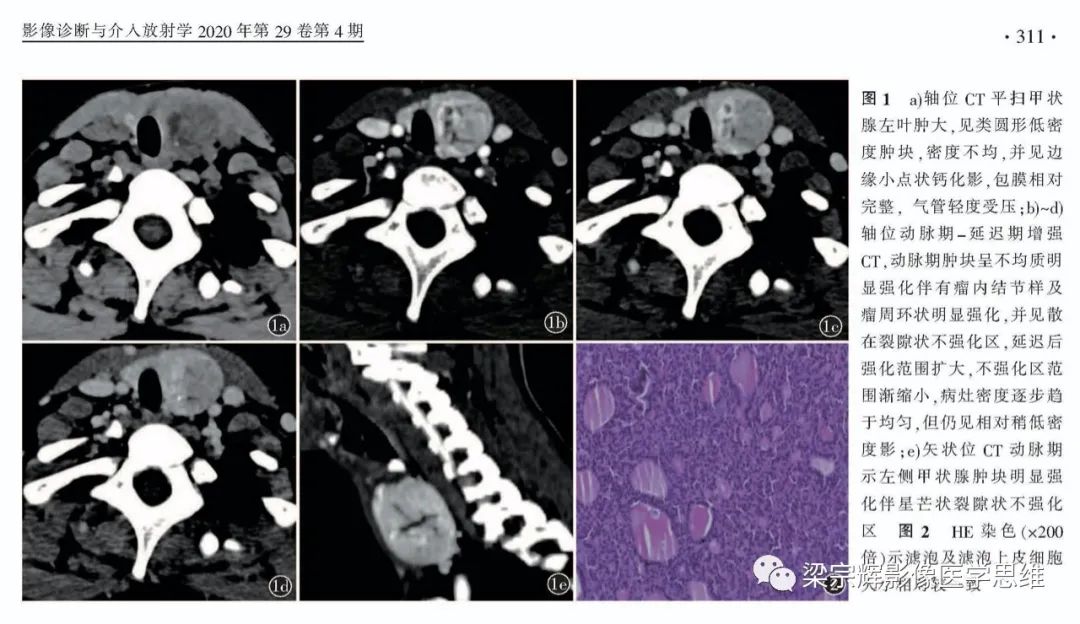

【病例】甲状腺腺瘤1例影像诊断思维-1

【病例】甲状腺腺瘤1例影像诊断思维-2

【病例】甲状腺腺瘤1例影像诊断思维-3

【病例】甲状腺腺瘤1例影像诊断思维-4

【病例】甲状腺腺瘤1例影像诊断思维-5

【病例】甲状腺腺瘤1例影像诊断思维-6